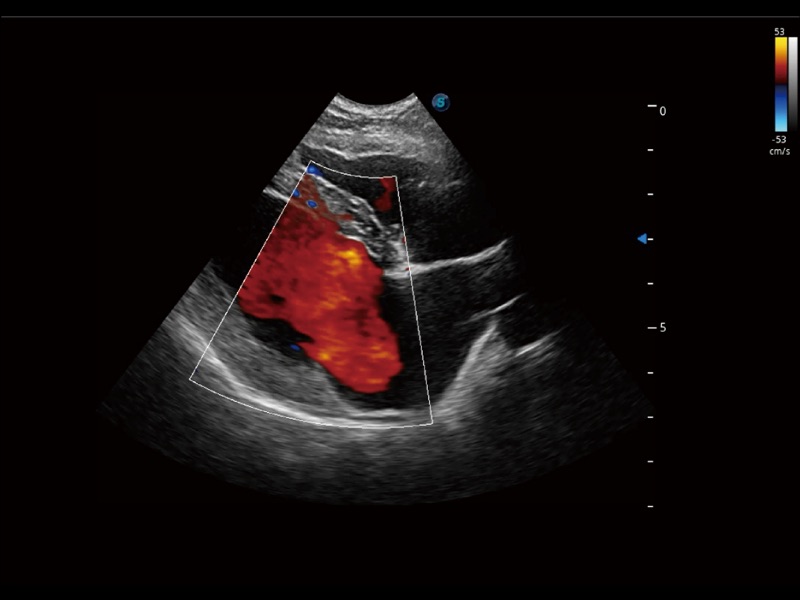

优异的基础图像

(犬)胎儿主动脉弓立体血流